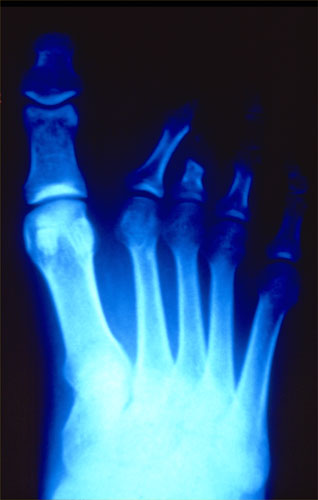

Iran The foot of a 14-year-old girl whose toes were clamped by ­revolutionary guards for wearing make-up. Photograph: Courtesy Hermann Vogel